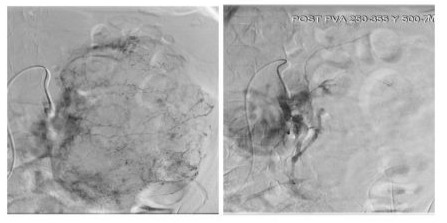

In patient B, the risk of surgical resection was found to be higher due to patient’s age and comorbidities. To reduce bleeding risk, selective embolization of tumor branches was successfully carried out (figure 5), with no adverse effects observed. Four months later, the lesion had decreased in size, so we performed an open partial nephrectomy due to the patient’s favorable general condition.

Figure 5: Before and after selective renal embolization.